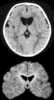

Glutaric acidemia type 1 is an inherited disorder in which the body is unable to completely break down the amino acids lysine, hydroxylysine and tryptophan. Excessive levels of their intermediate breakdown products (glutaric acid, glutaryl-CoA, 3-hydroxyglutaric acid, glutaconic acid) can accumulate and cause damage to the brain (and also other organs), but particularly the basal ganglia, which are regions that help regulate movement. [Source: Wikipedia ]